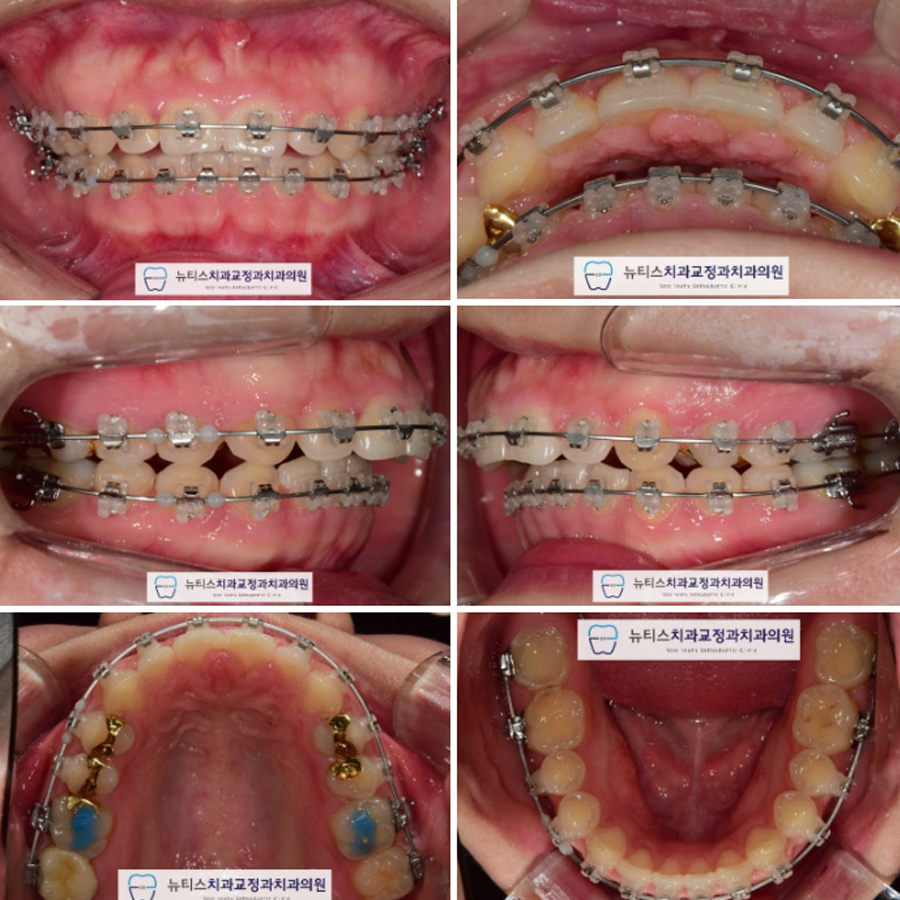

¹è¿ ÈÄ »çÁøÀÔ´Ï´Ù.

»ó¾Ç¿¡ ³²¾ÆÀÖ´ø °ø°£À» ´Ù ´Ý¾Ò½À´Ï´Ù.

Ãø¸é »çÁø¿¡¼ º¸½Ã¸é

¿©ÀüÈ÷ Ä¡¾ÆÀÇ µ¹ÃâÀ» È®ÀÎÇÒ ¼ö ÀÖÀ¸¸ç

±³ÇÕ°ü°è°¡ ¸ÂÁö ¾Ê½À´Ï´Ù.

ÀÌ¿¡ #±¸¼µ¿±³Á¤Ä¡°ú ÀÎ ÀúÈñ ´ºÆ¼½º¿¡¼´Â

»ó¾Ç Á¦ 1 ¼Ò±¸Ä¡¸¦ ¹ßÄ¡Çϰí

µ¹ÃâµÈ ¾Õ´Ï¸¦ ³Ö°í ±³ÇÕÀ» °³¼±Çϱâ·Î ÇÏ¿´½À´Ï´Ù.

*ÃÊÁø ´ç½Ã ¹ßÄ¡¸¦ ¸ÕÀú ÇÒ ¼ö ÀÖ¾úÀ¸³ª

Ʋ¾îÁü Á¤µµ°¡ ½ÉÇÏÁö ¾Ê°í »ó¾Ç¿¡ °ø°£ÀÌ

Á¸ÀçÇÏ¿© ¹è¿ ¸ÕÀú ½ÃÇà ÈÄ ¹ßÄ¡ °èȹÀ» Çß½À´Ï´Ù.

¹ßÄ¡´Â ºñ°¡¿ªÀû Ä¡·áÀ̹ǷÎ

ÃÖ´ëÇÑ ½ÅÁßÇÏ°Ô ÁøÇàÇÏ¿´½À´Ï´Ù.